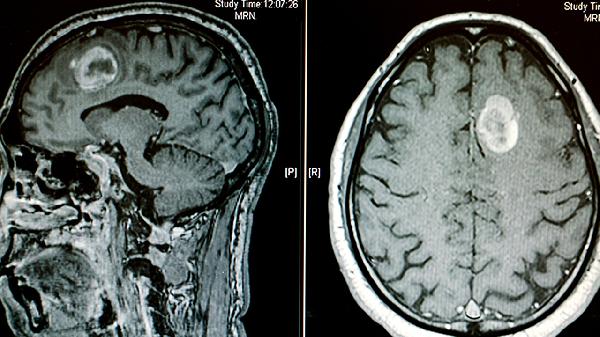

新生兒腦水腫主要表現(xiàn)為前囟膨隆、嗜睡或易激惹、喂養(yǎng)困難、肌張力異常及呼吸不規(guī)則。這些癥狀可能由缺氧缺血性腦病、顱內(nèi)出血、感染、代謝紊亂或先天性畸形等因素引起。